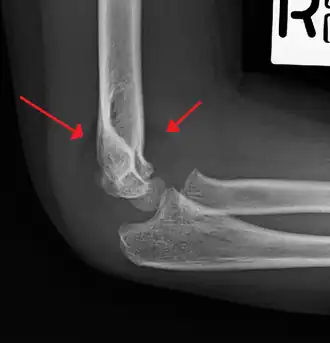

| An elbow X-ray showing a displaced supracondylar fracture in a young child | |

A supracondylar humerus fracture is a fracture of the distal humerus just above the elbow joint. The fracture is usually transverse or oblique and above the medial and lateral condyles and epicondyles. This fracture pattern is relatively rare in adults, but is the most common type of elbow fracture in children.[1] In children, many of these fractures are non-displaced and can be treated with casting. Some are angulated or displaced and are best treated with surgery. In children, most of these fractures can be treated effectively with expectation for full recovery.[2] Some of these injuries can be complicated by poor healing or by associated blood vessel or nerve injuries with serious complications.

A supracondylar humerus facture is diagnosed by x-ray and the injured limb will be examined to assess the surrounding soft tissue, neurovascular status, and to identify any other injuries to the affected area.[5] Pain, swelling, and deformity near the elbow or arm area is common and a bleed near the fracture may result in an effusion in the elbow joint. With severe displacement, there may be an anterior dimple from the proximal bone end trapped within the biceps muscle. The skin is usually intact. If there is a laceration that communicates with the fracture site, it is an open fracture, which increases infection risk. For fractures with significant displacement, the bone end can be trapped within the biceps muscle with resulting tension producing an indentation to the skin, which is called a "pucker sign".

Diagnosis is confirmed by x-ray imaging. Antero-posterior (AP) and lateral view of the elbow joint should be obtained. Any other sites of pain, deformity, or tenderness should warrant an X-ray for that area too. X-ray of the forearm (AP and lateral) should also be obtained for because of the common association of supracondylar fractures with the fractures of the forearm. Ideally, splintage should be used to immobilise the elbow at 20 to 30 degrees flexion in order to prevent further injury of the blood vessels and nerves while doing X-rays. Splinting of fracture site with full flexion or extension of the elbow is not recommended as it can stretch the blood vessels and nerves over the bone fragments or can cause impingement of these structures into the fracture site.[3]